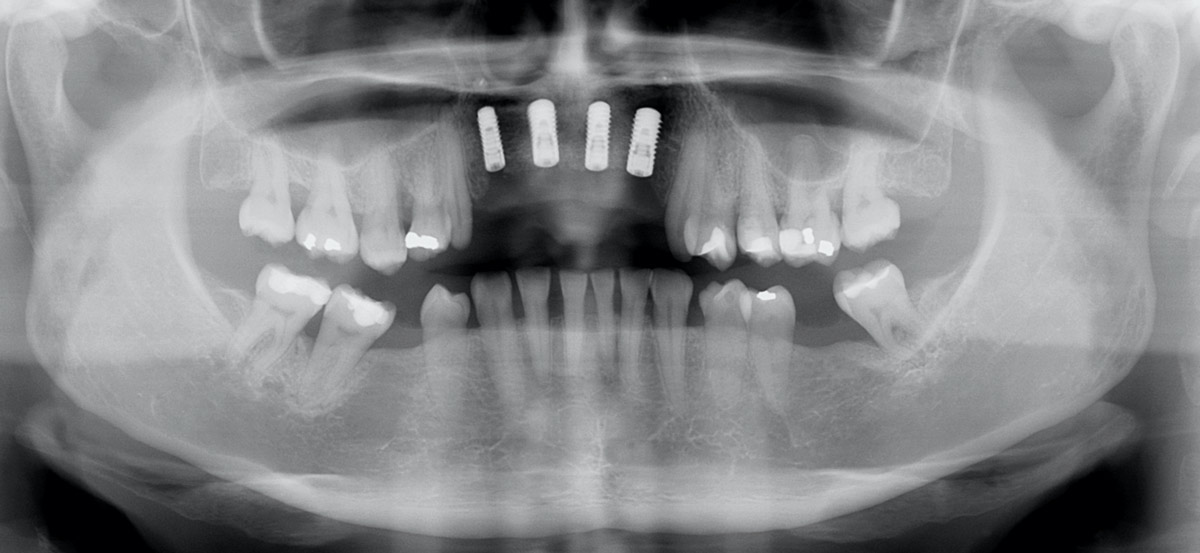

2/17 - Pre-operative x-ray scan: severe bone loss around three failing implantsRestoration of all four incisors with maxgraft® bonebuilder - Dr. Dr. Dr. O. Blume